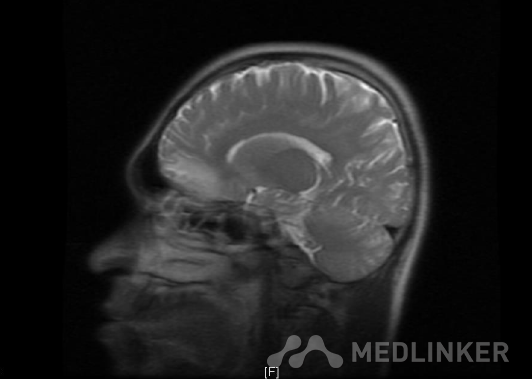

MR:双侧额叶及左侧颞叶异常信号,结合病史,多考虑脑挫裂伤(亚急性-慢性期);双侧下鼻甲肥厚。左侧蝶窦黏膜增厚。

诊断:1.多发脑挫裂伤2.蛛网膜下腔出血3.枕骨骨折 入院后积极予以预防癫 痛、预防脑血管痉挛、营养神经、护胃等对症支持治疗.